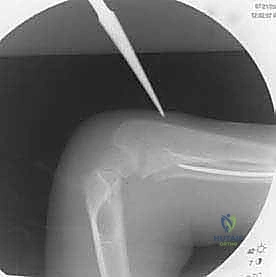

التشخيص الشعاعي الدقيق

في عيادة الأستاذ الدكتور محمد هطيف، لا يتم الاعتماد على الفحص السريري فقط. يُعد التشخيص الشعاعي الدقيق حجر الزاوية في تحديد خطة العلاج:

- الأشعة السينية (X-rays): يتم أخذ صور بأوضاع مختلفة (أمامي خلفي AP وجانبي Lateral). يصر الدكتور هطيف دائماً على أن تشمل الأشعة المفصل الذي يعلو الكسر (الكوع) والمفصل الذي يليه (الرسغ) لضمان عدم وجود كسور أو خلوع خفية (مثل كسور مونتيجيا أو جاليازي).

تُجرى العملية تحت التخدير العام لضمان راحة الطفل التامة. يتم تعقيم الذراع بالكامل وتغطيتها بالستائر الجراحية المعقمة. يُستخدم جهاز الأشعة السينية المتحرك (Fluoroscopy / C-arm) طوال العملية لتوجيه الجراح بدقة.

3. فتح المداخل الجراحية (Incision)

* لعظم الزند: يتم عمل شق صغير بالقرب من الكوع (تحت الناتئ الزجي).